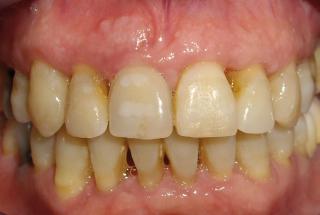

Clinical cases

MPI closely monitors clinical cases in the market to ensure their correct functioning and successful outcome.